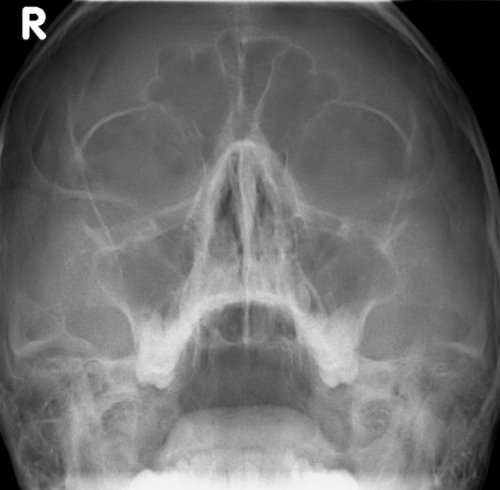

Poskiontelotulehdus oikealla

Kuva 1.

Poskiontelotulehdus oikealla. Kuutamokuva: oikeassa poskiontelossa runsas limakalvoturvotus sinuiitin merkkinä. Vrt. normaali sinusröntgenlöydös «Normaali sinusröntgenlöydös»1

.

Kuva: Tatu Kemppainen